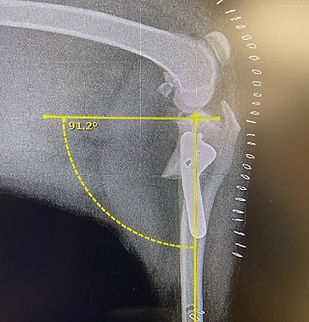

TPLO (Tibial Plateau Leveling Osteotomy) Procedure

Knee injuries caused by CCL ligament and meniscal tears

Rigid stabilization placing permanent stainless pins and bone plating

The TPLO procedure is the best method to repair a cranial cruciate ligament (CCL) rupture. The CCL is analogous to the anterior cruciate ligament (ACL) in humans. TPLO surgery helps to stabilize the stifle joint and reduce the likelihood of further osteoarthritis progression. TPLO is the most common procedure for dogs with a cruciate tear and requires a specialty surgeon to perform this procedure.

Dr. Sept has extensive experience in TPLO surgery, and he’s completed over 800 TPLO procedures with excellent results. Proper healing and recovery during the initial 10-14 days after surgery is closely monitored by Dr. Sept and throughout the required recovery timeline process.